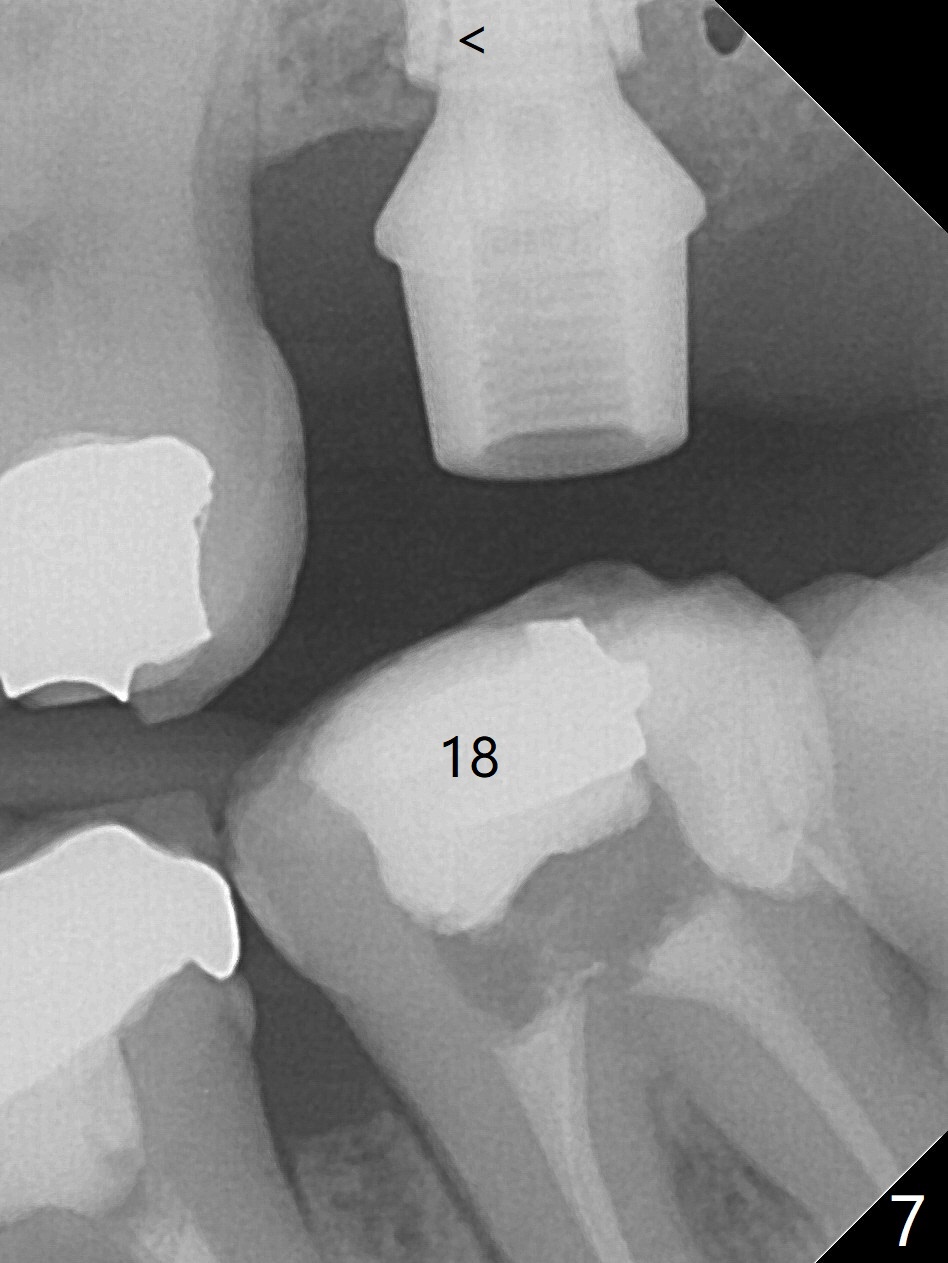

Designed osteotomy depth is 7.3 mm IS drill with 4 rings at #15. In fact osteotomy is created using 2.2 mm drill with 2 rings (sinus membrane barely visible from the osteotomy) and 3-4 mm ones with 3 rings. With an amalgam carrier of bone graft, sinus lift is initiated with 4x9 mm dummy implant (Fig.1). After loaded with totally 5 amalgam carriers of bone graft repeatedly with the 4x9 mm dummy implant, a 5x9 mm implant is placed with ~ 25 Ncm. After insertion of a 6x4(2) mm abutment, sticky bone cut into pieces (Fig.2) is inserted to peri implant space (Fig.3 *), followed by PRF and an immediate provisional. The latter dislodges 7 days postop; the socket starts to heal (Fig.4); the bone graft seems to be fixed in place. The provisional is reseated (no cement, Fig.5) without fear of its dislodgement again. The patient returns for cleaning 1 year 7 months postop (Fig.6,7). The socket heals, while the abutment is incompletely seated (Fig.7 <). Percussion at #18 disappears post RCT, whereas periapical radiolucency appears post RCT (compare Fig.8,9). When the 6x4(2) mm incompletely seated abutment is removed, the implant well is dirty. The smaller abutment with longer cuff is seated fully (Fig.10).